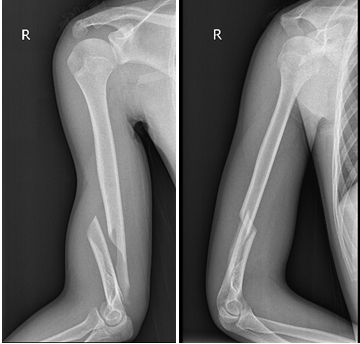

主治医师唐聪给小强申请了影像检查

检查结果显示

他的右肱骨下段螺旋性骨折

骨头错位明显

X光可见小强的右肱骨下段出现骨折。